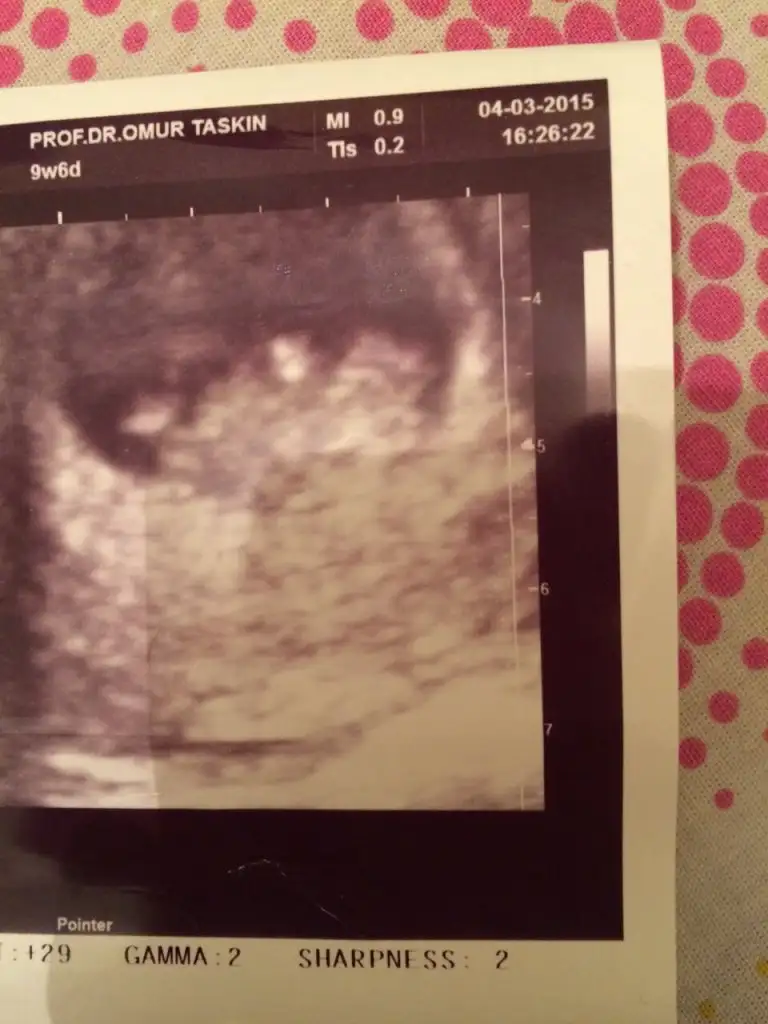

dr soylemeden siz gorun genital nub teorisi ( bebegin cinsiyeti)

kızlar benim bebeğimede bakar mısınız yorum yağar mısınız

kızlar 9+1 dedi cinsiyet tahmin edebilir misiniz